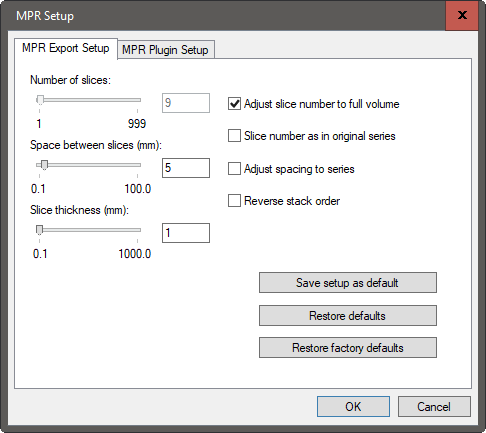

| MPR beállítási lehetőségek | Funkció | Alapértelmezett |

| Szeletek száma | Jelölje be a Szelet száma mint az eredeti sorozatban jelölőnégyzetet, írja be a számot, vagy használja a csúszkát | Ugyanaz, mint az eredeti sorozat |

| Szeletek közötti távolság (mm-ben) | Jelölje be a Távolság beállítása sorozathoz jelölőnégyzetet, írja be a számot a megfelelő mezőbe | 5 |

| Szeletvastagság (mm-ben) | Módosítsa a számot a megfelelő mezőben | 1 |

| Fordított halmazsorrend | A halmazsorrend megfordítása úgy, hogy a görgetés összhangban legyen a többi sorozattal | |

| Beállítás mentése alapértelmezettként | Az aktuális beállítások mentése alapértelmezettként | |

| Alapértelmezettek visszaállítása | Visszaállítja az utoljára mentett beállításokat | |

| Gyári beállítások visszaállítása | Visszaállítja a gyári beállításokat |